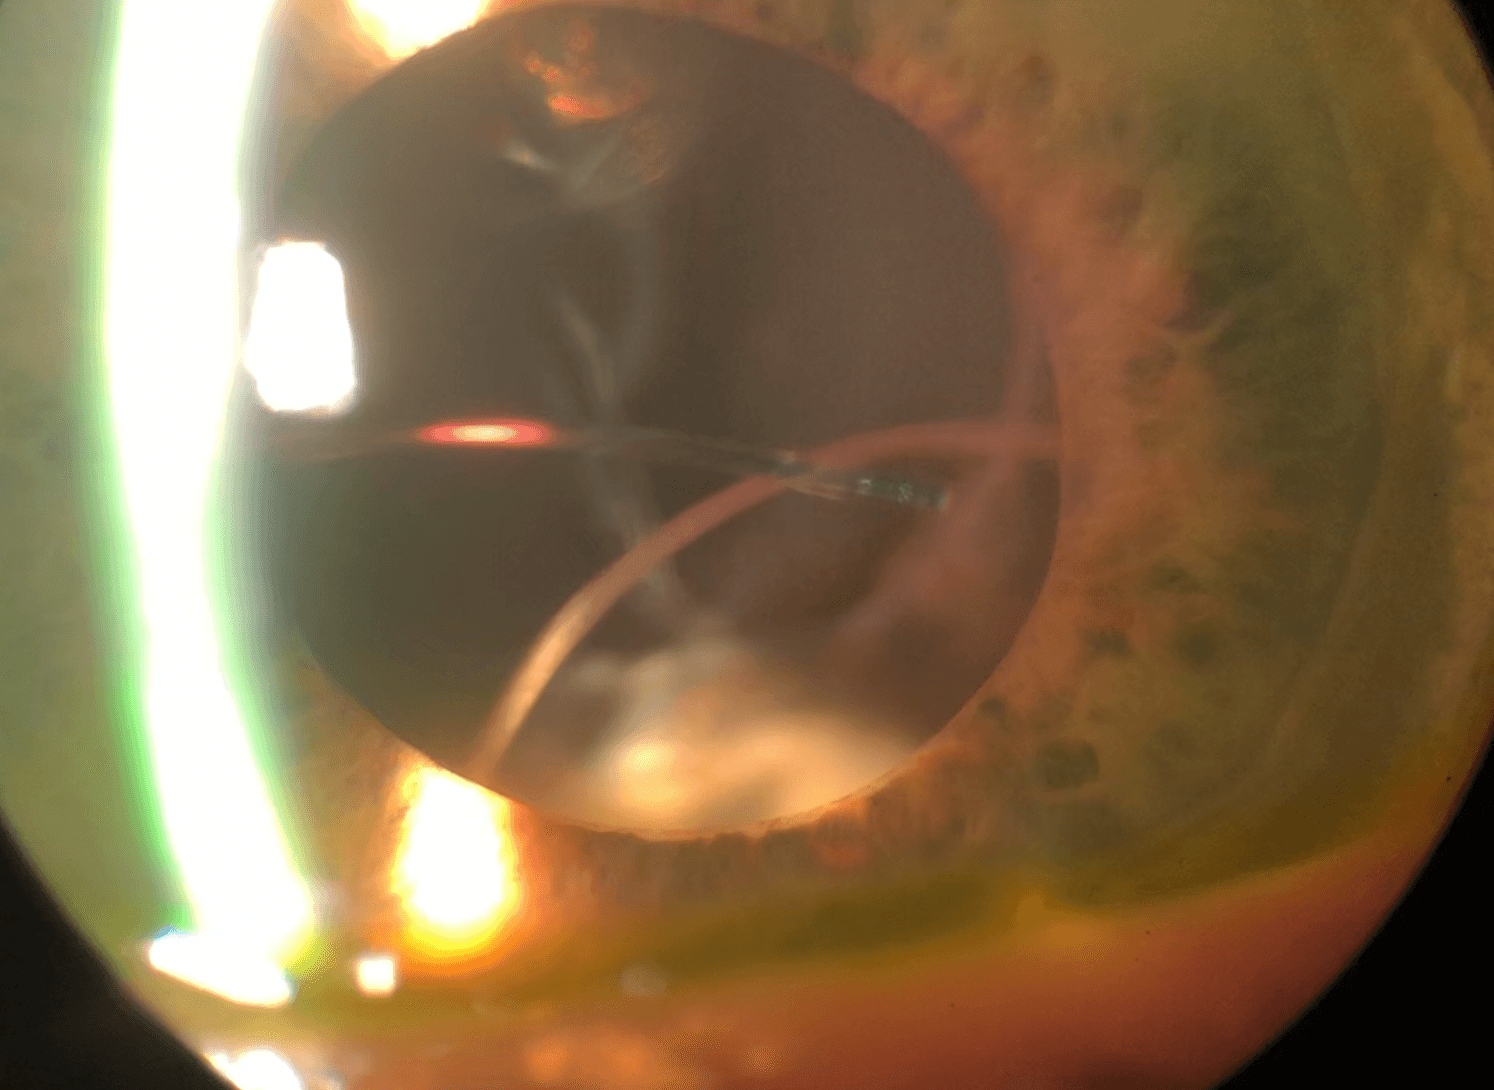

Figure 1 demonstrates a dislocated IOL due to advanced pseudoexfoliation.

Figure 1. Photo courtesy of Eric Rosenberg, DO MSE